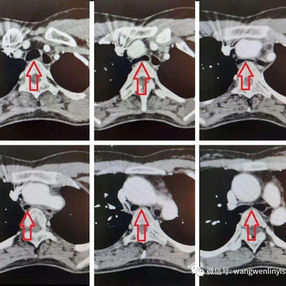

The patient’s thoracic spine is unnaturally flat with a slight forward curvature at the upper thoracic vertebrae, reducing the distance between it and the anterior chest wall. Additionally, the ascending aorta is dilated, and the trachea is noticeably compressed, particularly severely at the start of the aortic arch. The patient was ultimately diagnosed with flatback syndrome combined with severe tracheal stenosis.

2. The upper portion of the sternum and the first and second ribs on each sides were excised, revealing that the ascending aorta, aortic arch were closely adjacent to the heart and sternum. Additionally, significant enlargement of the thymus was observed.

3. The thymus was excised and the anterior chest wall was reconstructed using a custom digital material tailored from the patient’s chest data. This ensured a clearance of about 2cm between the chest wall and the ascending aorta.

4. The trachea was confirmed to be free of compression, with the airway pressure reduced from 23 to 12.